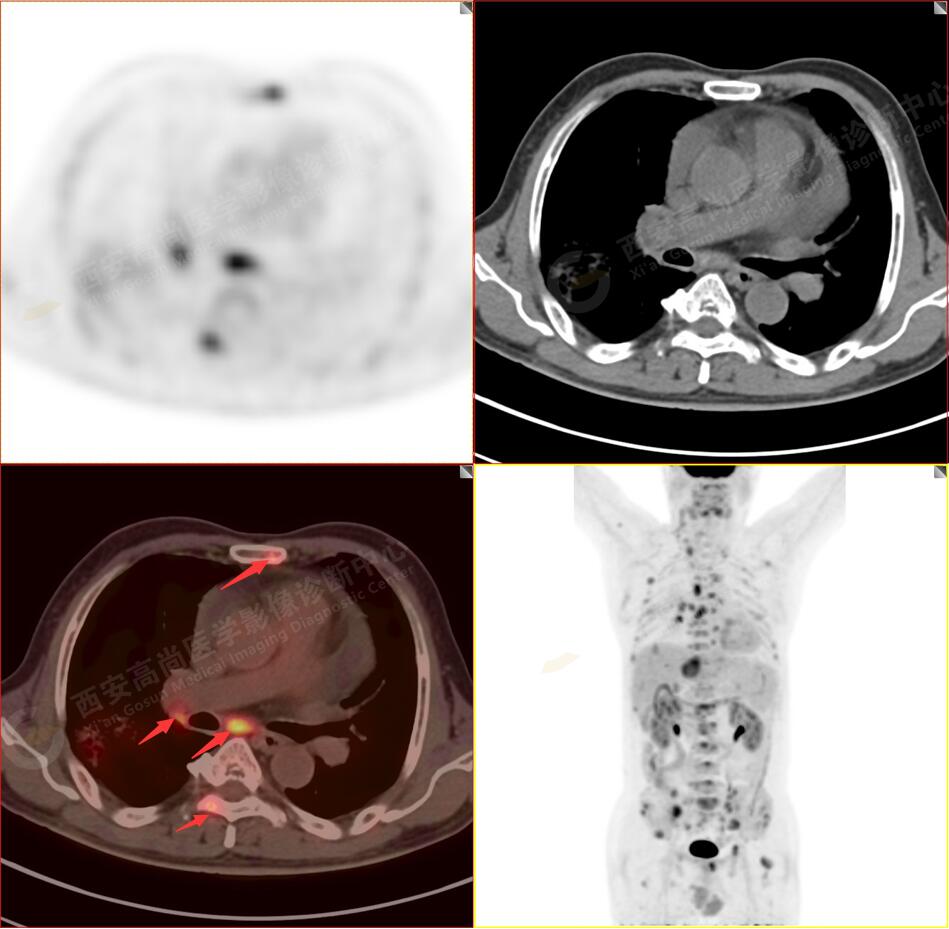

2.以下為全身多發(fā)轉移灶

2.雙肺內(nèi)彌漫性分布大小不等實性小結節(jié)灶及粟粒狀高密度影,均未見FDG代謝明顯異常增高,均多考慮為癌性淋巴結炎及轉移性病變。

3.右側頸部(Ⅱ-Ⅴ區(qū))、右側腋窩區(qū)、右側肺門及縱隔(1R、1L、2、4、6、7組)、肝門區(qū)多發(fā)腫大淋巴結,呈不同程度異常增高,均考慮為淋巴結轉移。